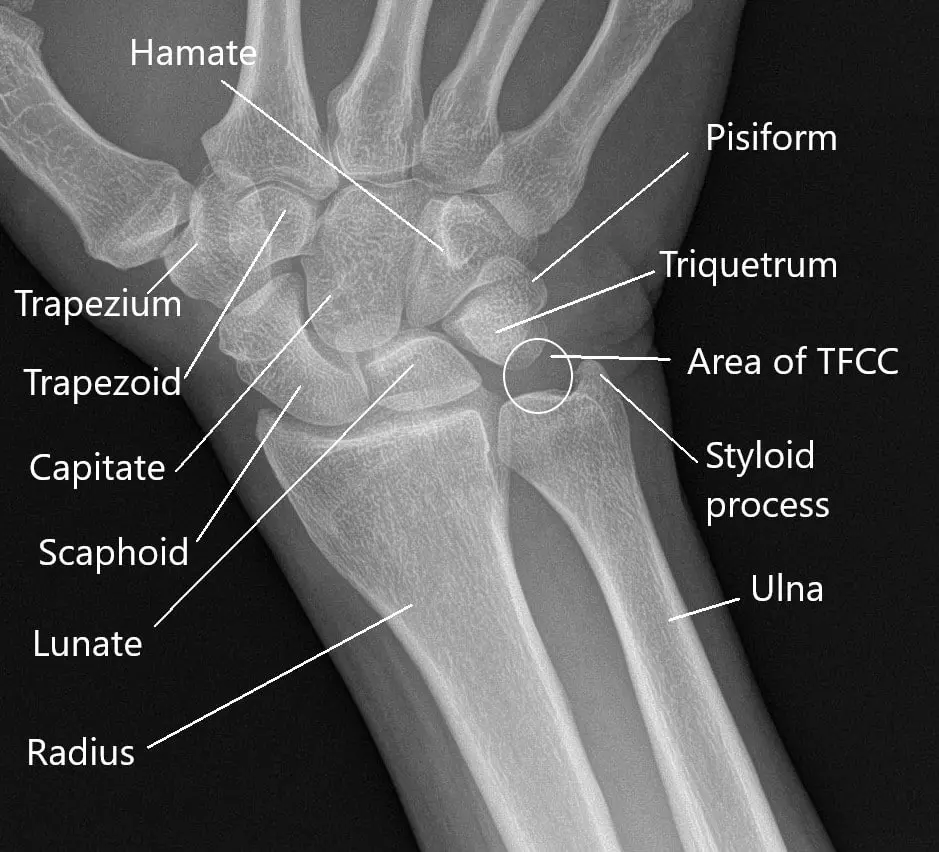

The wrist joint is made of a number of small joints connecting the forearm with the hand. There are 8 bones in each wrist connecting with bones of lower forearm and hand. Besides bones, there are tendons and ligaments forming an essential part of the wrist joint. Various structures such as nerves and blood vessels pass across the wrist joint in a small space.

- Triangular fibrocartilage complex (TFCC) is a small tissue that provides a cushion to the small bones on the pinky side. Tears of TFCC may cause chronic pain and instability.

- Kienbock disease is the avascular necrosis of the lunate bone in the wrist. The blood supply of the bone gets disrupted which results in bone death. The lunate plays an important role in the smooth movements of other bones. The disease usually affects young adults.

Radiological examination is generally undertaken. An X-ray helps to locate any fractures and signs of arthritis. A CT scan is helpful to look for fractures not visible on an X-ray. MRI helps to look for inflammation and swellings of the wrist as well as the nerve entrapments.